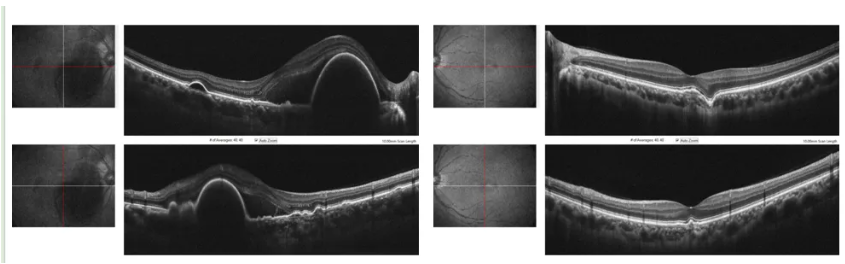

病例二:急性起病的青年PCV

患者为一名35岁男性,因“双眼视力下降4天”就诊,否认全身特殊慢性病史,既往无高度近视。

眼科查体

视力:右眼0.4,左眼0.1。

OCT

FFA+ICGA

病例三:伴脉络膜高渗透性的中年PCV

患者为一名45岁男性,因“左眼视力下降1月”就诊,否认全身特殊慢性病史,既往无高度近视。

视力:右眼0.8,左眼0.4。

FFA+ICGA:

左眼典型的BVN和息肉,晚期部分冲刷现象,是PCV的特征改变。同时,造影影像中伴有脉络膜血管高渗透性改变。

病例四:单眼PCV伴对侧眼最佳矫正视力低下

患者为一名41岁男性,因“左眼视力下降半月余”就诊,否认全身特殊慢性病史,既往无高度近视。

视力:右眼0.05,左眼0.6。

右眼典型的BVN和息肉,晚期部分冲刷现象,是PCV的特征改变。同时,造影影像中伴有脉络膜血管高渗透性改变。

病例汇总与讨论

上述4例患者发病年龄为35~45岁,均低于PCV常见发病年龄段。病例一揭示了年轻PCV可被长期误诊为慢性CSC,关键在于通过ICGA识别隐匿的BVN和息肉,并注意其常伴发的脉络膜高渗透性特征;病例二展示了PCV在青年中也可急性起病;病例三、四进一步印证了脉络膜高渗透性在年轻PCV中的常见性。所有病例的ICGA均显示出典型PCV特征,支持其诊断。病例一的长期随访提示,部分年轻PCV对抗VEGF治疗的反应可能不佳,表现为依赖性治疗和易复发,治疗挑战更大。